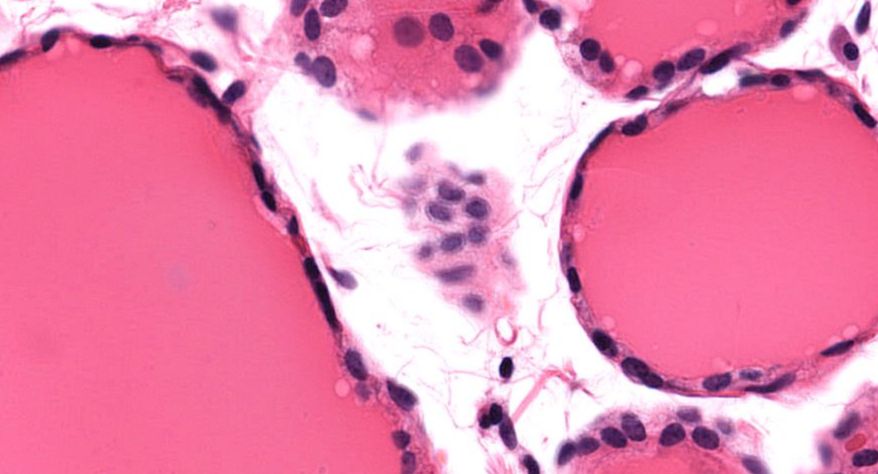

低倍镜观察:1. 被膜:由薄层结缔组织组成。2. 实质:由许多大小不等的滤泡构成。滤泡壁是单层立方上皮细胞,滤泡腔内充满粉红色匀质胶状物,滤泡之间的结缔组织内有丰富的血管。高倍镜观察:1. 滤泡:滤泡壁的单层滤泡上皮细胞一般呈低柱状或立方状,胞质着浅色,细胞核呈圆形。滤泡腔内充满了粉红色匀质胶质。2. 滤泡旁细胞:体积较大,呈圆形或椭圆形;细胞核较大,呈圆形,着色较浅,细胞质染色也较浅。细胞或嵌在滤泡壁上或成团分布于滤泡之间。3. 间质:由结缔组织组成。位于滤泡之间。其中含有丰富的毛细血管及三五成群的滤泡旁细胞。

5.滤泡旁细胞1

7.滤泡旁细胞2